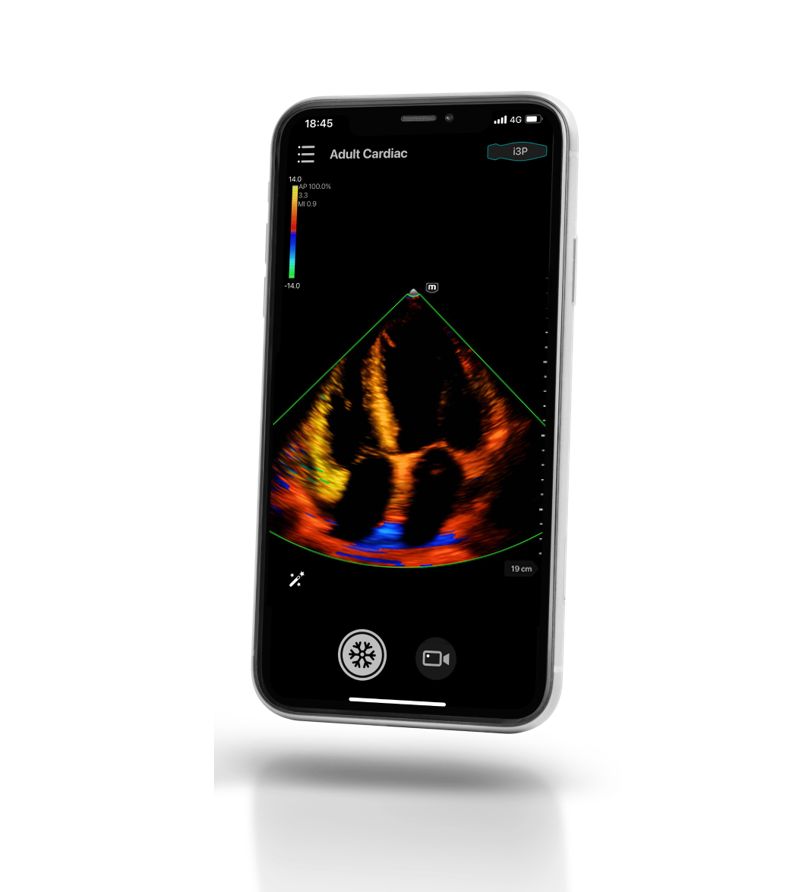

Wireless handheld ultrasound system

TE Air

TE Air, the new generation wireless handheld ultrasound system from Mindray, is designed to meet these higher clinical requirements, such as Emergency and Critical Care. By combining premium capabilities with a wireless experience, efficient connectivity, and a robust design for unpredictable environments, the TE Air wireless handheld ultrasound system helps to improve clinicians' confidence and efficiency in unprecedented ways.

TE Air, the new generation wireless handheld ultrasound system from Mindray, is designed to meet these higher clinical requirements, such as Emergency and Critical Care. By combining premium capabilities with a wireless experience, efficient connectivity, and a robust design for unpredictable environments, the TE Air wireless handheld ultrasound system helps to improve clinicians' confidence and efficiency in unprecedented ways.

Powered by the eWave platform and the second-generation Single Crystal technology, TE Air delivers high-quality images with low power consumption for accurate decision-making.

- The App allows one-hand operations for enhanced efficiency

- An intuitive user interface for ease of use

- Simple to operate with gestures

- The App allows one-hand operations for enhanced efficiency

- An intuitive user interface for ease of use

- Simple to operate with gestures